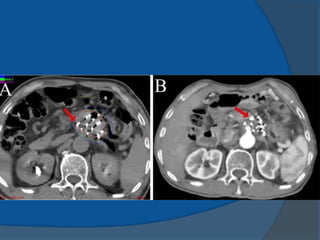

1980 Martinez and colleagues newbrachytherapy approaches to the treatment of prostate cancer were initiated temporary seeds inserted using a transperineal approach Dr Puthawala and colleagues pioneered a temporary seed technique of placing the needles, while visualizing them through an open laparotom Dr Whitmore and colleagues MSKCC began to insert I-125 seeds as a sole treatment through an open incision mid- 1980s transrectal ultrasound-guided, template-guided I-125 implantation procedure has become the primary technique of permanent seed implantation

1983 Hans HenrikHolm use of transrectal ultrasound to visualize the permanent placement of I-125 seeds via needles inserted through the perineum directly into the prostate implanting I-125 seeds into cancerous prostates, under the direction of axial imaging from a rectal probe mounted on a sledge-stepper (stepping unit). 1985 Blasko and Ragde the first transperineal, ultrasound- guided approach in the United States ultrasound-guided approach resulted in increased accuracy of needle and seed placement and relatively even distribution of seeds throughout the prostate it allowed computerized treatment planning of the implant rather than the use of simple nomograms ensuring the proper number, strength, and positioning of radioactive sources.